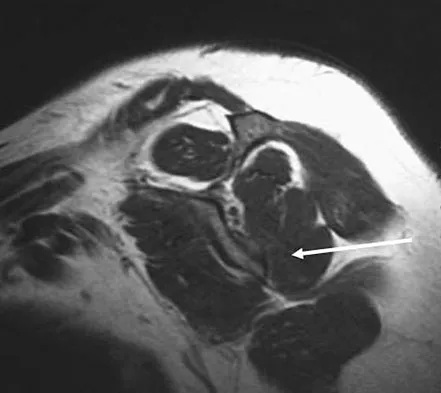

A 13-year-old girl who competes in gymnastics reports the insidious onset of lateral left elbow pain over the past 6 months. She also notes occasional catching episodes in the elbow; however, she denies any history of trauma. Examination reveals tenderness over the lateral epicondyle and extensor muscle origin. The elbow is stable and has full flexion, but lacks 10 degrees of full extension. An AP plain radiograph and an MRI scan are shown in Figures 17a and 17b. Management of the elbow should consist of

Explanation

The radiograph and MRI scan show osteochondritis dissecans of the capitellum, and the patient's history suggests a loose body. The treatment of choice is arthroscopic removal of the loose body and microfracture of the crater. Excision of the radial head, a cortisone injection, or tennis elbow release does not treat the pathology in the capitellum. Nonsurgical treatment would not relieve the mechanical symptoms of the loose body or promote healing in the crater. Baumgarten TE, Andrews JR, Satterwhite YE: The arthroscopic classification and treatment of osteochondritis dissecans of the capitellum. Am J Sports Med 1998;26:520-530. Jackson DW, Silvino N, Reiman P: Osteochondritis in the female gymnast's elbow. Arthroscopy 1989;5:129-136.